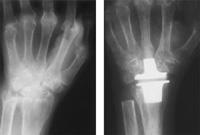

Wrist joint replacement

X-ray of a wrist with osteoarthritis before (left) and after (right) wrist replacement surgery using a two-part metal and polyethylene implant.

Reproduced with permission from Carlson JR, Simmons BP: Total Wrist Arthroplasty. J Am Acad Orthop Surg 1998;6:308-315.